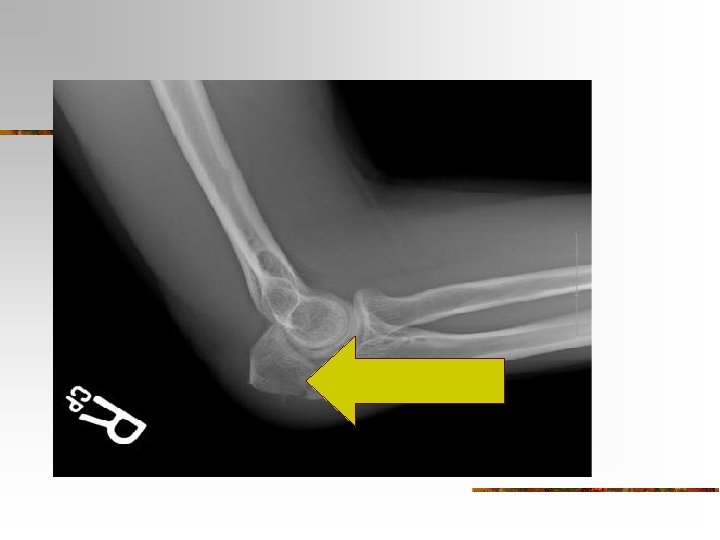

n n n TROCHLEA - a spoolshaped surface that articulates with the ulna. CORONOID FOSSA – a depression that receives part of the ulna when the forearm is bent. OLECRANON FOSSA a depression on the back of the bone that receives the ulna when the forearm is straightened.

Ulna Bone Surface Markings n n n The olecranon forms the prominence of the elbow on the proximal end. The coronoid process projection on the proximal, helps to hold the trochlea Trochlear Notch – depression formed by the olecranon and coronoid process

Fractures